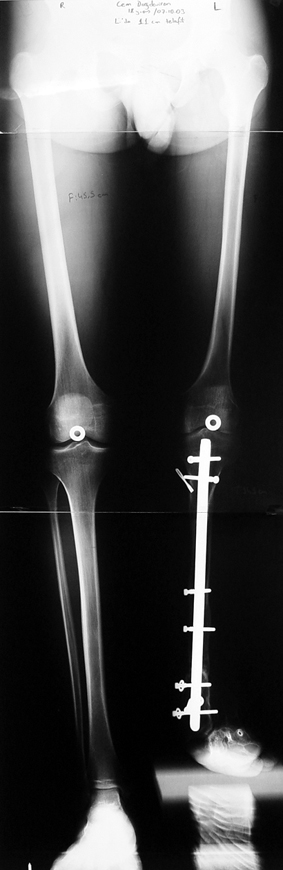

3. POSTTRAUMATIC LOWER LIMB SHORTNESS (MALUNION)

This type of shortness occurs after a fracture heals in a shortened position. Most cases are seen in adults and can be treated with one lengthening operation. Additional deformities can be corrected simultaneously. Most of these cases can be treated with lengthening over nail or just corrections and intramedullary nailing.